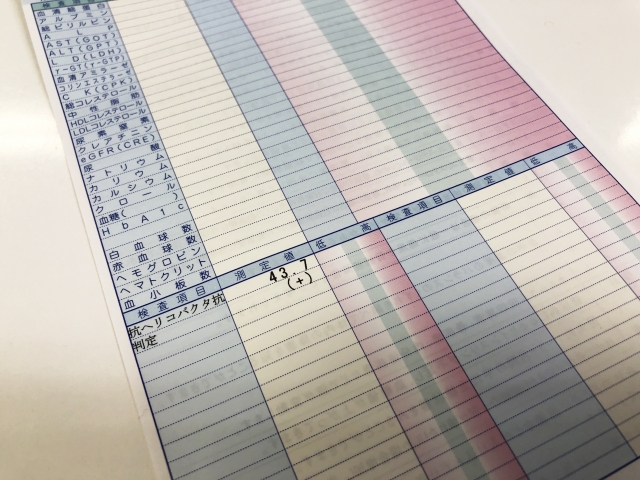

3か所から生検を行いましたが、病理検査の結果はいずれも「がんなし」でした。それでもスキルス胃がんの可能性が高いと判断し、総合病院で精密検査を受けていただくことにしました。